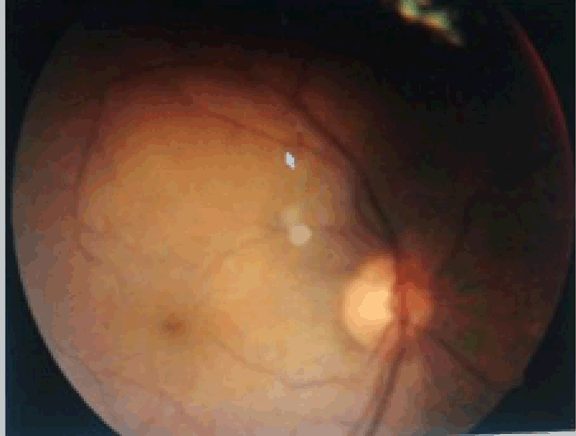

A 35-year-old male patient presented to our institution with complaints of blurring of vision in both eyes and headache for 15 days. The patient had a history of perforated bacterial corneal ulcer five months before in his left eye leading to adherent leucoma. Best corrected visual acuity in both eyes was finger counting close to face. Anterior segment examination of both eyes showed few KPs, +1 cells and mild retrolental flare while left eye had adherent leucoma in addition to above findings. (Figure 1) On fundus examination of right eye exudative retinal detachment and few choroidal lesions over fundus were detected, (Figure 2) while left eye fundus could not be accessed due to adherent leucoma. The intraocular pressure was 12 mmHg in both eyes. The systemic evaluation did not reveal any evidence of a focus of infection, vitiligo, alopecia, dysacousia or meningeal signs. The erythrocyte sedimentation rate (ESR), chest X-ray, enzyme-linked immunosorbent assay (ELISA) for toxoplasma, venereal disease research laboratory test (VDRL) test and audiometry were within normal limits. Ultrasonography for the posterior segment revealed retinal detachment in both eyes. (Figure 3) (Figure 4) The fluorescein angiogram of the right eye showed multiple hyperfluorescent spots at the level of the retinal pigment epithelium in the venous phase which persisted in the late phase. In addition, there was coalescence of the dye in the area of the exudative detachment. Based on the typical history and clinical signs, a diagnosis of sympathetic ophthalmitis was made and the patient was initiated on high dose intravenous steroids with 1 gram methyl prednisolone for three days followed by oral steroids 50 grams in single dose for one week which was then slowly tapered over the next three months. Resolution of the exudative detachment with recovery of best corrected visual acuity to 20/200 in both eyes occurred after 72 hours following the initiation of intravenous steroids. (Figure 5) At one week patient became asymptomatic with a visual acuity of 20/60 in right eye and 20/80 in left eye with no evidence of disease activity. Visual acuity improved to 20/30 in right eye and 20/80 in left eye at one month follow-up and remained the same with no sign of relapse. | ||||||